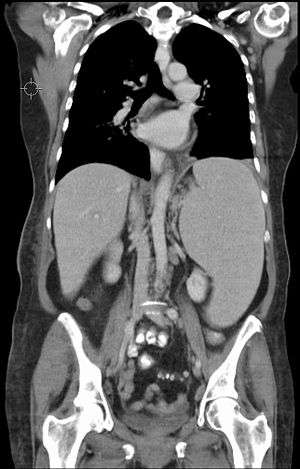

| CT scan showing splenomegaly in a patient with chronic lymphoid leukemia | |